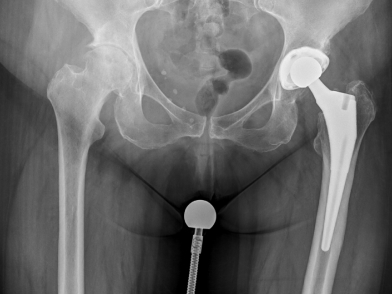

Πριν

Μετά

Η συνήθης προεγχειρητική αξιολόγηση του ασθενούς που προγραμματίζεται για ολική αρθροπλαστική ισχίου περιλαμβάνει πέρα από τη λήψη του ιστορικού και την κλινική εξέταση από το χειρουργό, τη διενέργεια προσθιοπίσθιων ακτινογραφιών σε όρθια θέση (αν είναι δυνατόν) της πυέλου, καθώς και προφίλ ακτινογραφίες του ισχίου, ενώ αποτελεί καλή πρακτική η λήψη ακτινογραφιών του σύστοιχου μηριαίου, ιδίως σε περιπτώσεις προηγούμενων ορθοπαιδικών χειρουργείων πιο περιφερικά. Οι βασικές εργαστηριακές εξετάσεις, ένα ηλεκτροκαρδιογράφημα, μία ακτινογραφία θώρακος καθώς και η προεγχειρητική εκτίμηση από αναισθησιολόγο, αλλά και σε περίπτωση που απαιτείται από καρδιολόγο ή άλλες ειδικότητες, περιλαμβάνονται επίσης σε αυτή τη φάση. Επιπλέον, η χειρουργική ομάδα θα αξιολογήσει τις προεγχειρητικές ακτινογραφίες και θα πραγματοποιήσει μία κατά προσέγγιση μέτρηση των εμφυτευμάτων (tempting) που θα χρησιμοποιηθούν, ώστε να υπολογιστεί το μέγεθος και ο προσανατολισμός τους, η προεγχειρητική διαφορά μήκους των σκελών και το πώς αυτή θα αποκατασταθεί μετά την εμφύτευση της αρθροπλαστικής, καθώς και άλλες τεχνικές λεπτομέρειες. Πριν από το χειρουργείο οι ασθενείς θα ενημερωθούν επίσης για το ενδεχόμενο ανάγκης για μετάγγιση αίματος τόσο διεγχειρητικά όσο και μετεγχειρητικά, ενώ θα τους ζητηθεί και να διαβάσουν και να υπογράψουν με τη βοήθεια και την υποστήριξη της χειρουργικής ομάδας το έντυπο συγκατάθεσης.